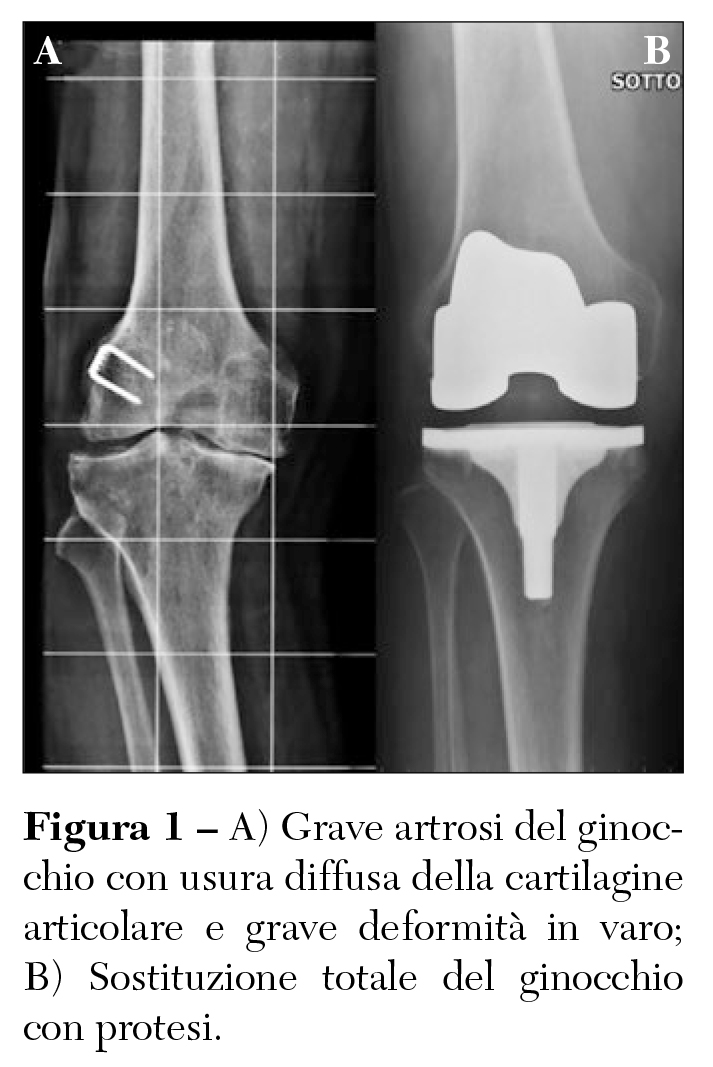

In base al livello e alla sede di usura è possibile eseguire alcuni differenti interventi chirurgici che prevedono la sostituzione protesica del ginocchio. Nelle forme più avanzate con grave usura dell’articolazione, compromissione dei legamenti articolari e grave deformità dell’arto inferiore è indicato eseguire un intervento di protesi totale che prevede la sostituzione di tutta l’articolazione del ginocchio (Figura 1).